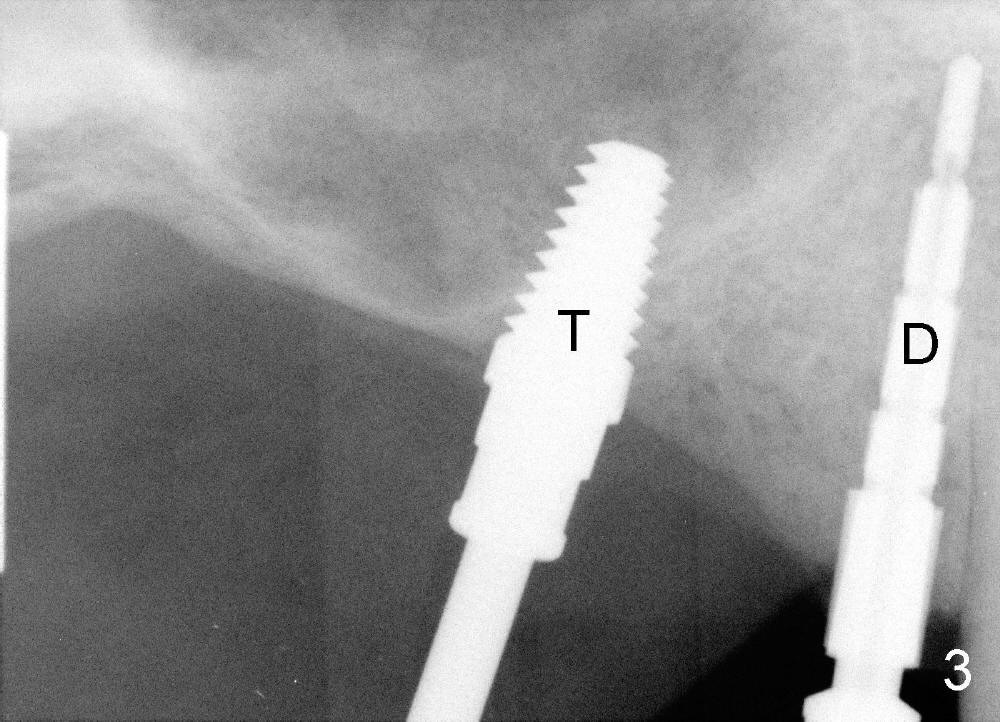

It appears that sinus graft is necessary for #3-5 implant placement (Fig.1). Mr. Wu says "Do whatever you think appropriate." But the framework partial denture is suddenly broken at the major connector. He cannot eat well. We do not have time to do sinus graft! Short implant is planned to be placed at the site of #3 (5x11 mm, Fig.1). After initial bone expansion until RT 2 mm (as mentioned above), two-mm pilot drills are inserted at the sites of #3 and 5 (Fig.2). The sinus floor is perforated at #3. The osteotomy for #3 is then moved mesially ~ 2 mm using osteotomes (RT 2-4mm). While bone expansion (osteotomes and taps) is being used to create osteotomy for #3, tapered drills for #5. Fig.3 shows 5x11 mm tap and 3.5x20 mm drill in place. Finally 6x11 mm and 4x20 mm implants are placed with >60 Ncm (Fig.4). The patient is also doing great nearly two weeks postop. A third implant is planned to be placed at the site of #5 1-3 months later.